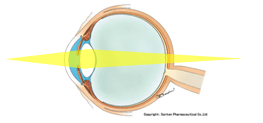

一般的なカメラは、ピンホールではなく、レンズを使用するのですが、レンズに入った光がフィルムにピッタリと焦点(ピント)があえば、明るく、キレイな画像を得ることができます。